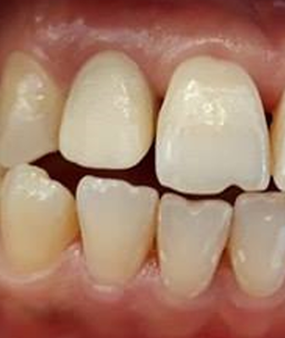

The patient I.M., 32 years old, presented for the restoration of the severely damaged upper right lateral incisor (tooth 12) following trauma (Figure 1).

Figure 1: Initial Situation.

She also exhibits anterior diastemas. The periapical radiograph reveals insufficient endodontic treatment and a periapical lesion (Figure 2).